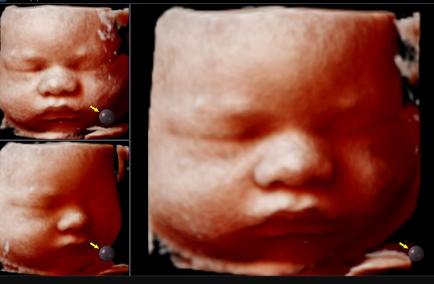

3D ultrasound imaging compiles multiple two-dimensional images to create a three-dimensional picture of your baby. This advanced technique provides detailed visuals of your baby’s features, offering a clear and lifelike image. Parents often choose 3d ultrasound Melbourne to get a more realistic view of their baby’s face and physical features, creating a deeper emotional connection.

4D Ultrasound: Real-Time Motion Capture

The 4d ultrasound Melbourne takes 3D imaging a step further by incorporating the dimension of time, resulting in live-action images. This allows you to see your baby in motion, capturing movements like kicking, stretching, and even facial expressions. Watching these moments in real-time provides an incredible bonding experience and a glimpse into your baby’s world before birth.

5D Ultrasound: The Ultimate in Image Quality

5D ultrasound represents the latest in ultrasound technology, enhancing the traditional 4D experience with superior clarity and depth. Using advanced rendering techniques, 5D ultrasounds produce highly detailed and realistic images, allowing you to see your baby with unprecedented clarity. This technology enhances Pregnancy ultrasound Melbourne the emotional experience and provides essential insights into your baby’s health and development.